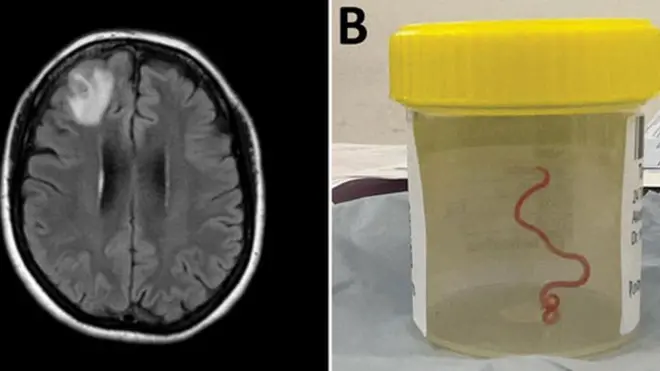

アメリカでこのほど、片頭痛をたびたび訴えていた男性の脳にサナダムシ(条虫)の幼虫が見つかった。生焼けのベーコンを食べたことと関係があるとみられている。

スキャン検査の結果、脳内にサナダムシの幼虫の嚢胞(のうほう)が発見されたという。

生焼けの豚肉を食べたことでサナダムシが体内に入っていたと思われる男性が、「不適切な手洗い」が原因で嚢(のう)虫症になったと医師団は見ている。

嚢虫症は、豚条虫としても知られる寄生虫、有鉤(ゆうこう)条虫の幼虫によって引き起こされる感染症の一種。脳内に嚢胞ができることもある。

男性は抗寄生虫薬と抗炎症薬が効き、その後完治したという。